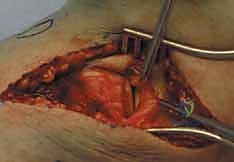

Crucially, the modern orthopedic surgeon must possess a heightened awareness of the posteromedial shear fragment. Historically underappreciated, this specific fracture morphology occurs when the knee is subjected to an axial load while in a flexed and varus position. The medial femoral condyle shears off the posteromedial aspect of the tibial plateau. This is not merely a radiologic curiosity; it represents a highly unstable fracture-dislocation variant. The posteromedial fragment often encompasses the insertion of the posterior cruciate ligament (PCL) and the meniscotibial ligaments. Failure to recognize and independently stabilize this fragment with dedicated posterior or posteromedial buttress plating will inevitably lead to catastrophic posterior subluxation of the femur and rapid varus collapse of the mechanical axis, regardless of the robustness of the lateral fixation.

The surgical approaches to the proximal tibia are fraught with neurovascular hazards. A deep, three-dimensional understanding of these structures is essential to prevent devastating iatrogenic complications. On the medial side, the saphenous nerve and the great saphenous vein course superficially. During the posteromedial approach, these structures must be identified early and gently retracted anteriorly. Injury to the saphenous nerve results in painful neuromas and sensory deficits along the medial aspect of the leg and foot, while damage to the vein can exacerbate post-operative edema and increase the risk of deep vein thrombosis.